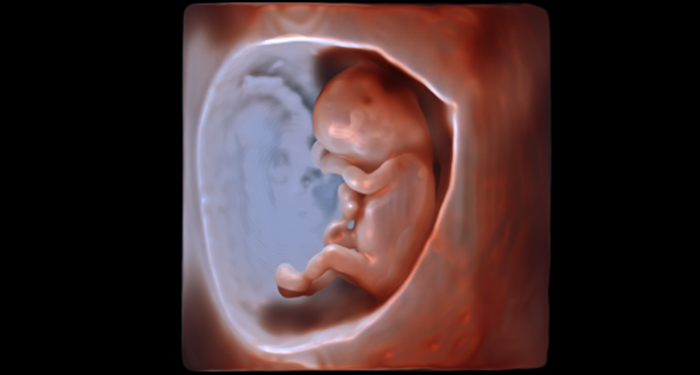

À chaque étape de la vie d’une femme, ou d’une vie en développement, les solutions d’échographie de Philips sont conçues pour augmenter la fiabilité du diagnostic, optimiser votre processus de travail et vous rapprocher de vos patientes. Dans les moments complexes, disposer du système d’échographie Philips peut vous aider à apporter à vos patientes les soins et le réconfort dont elles ont besoin.

Chez Philips, nous savons que la relation entre une femme et son gynécologue/obstétricien est, par nature, personnelle. Nous avons conçu nos solutions pour vous aider à entretenir une relation de confiance avec chacune de vos patientes. Chaque jour et chaque patiente apportent quelque chose de nouveau. Peu importe le défi diagnostique, vous avez besoin d’une imagerie échographique de la plus haute qualité pour prendre des décisions en toute confiance, même avec les patientes les plus difficiles sur le plan technique. Nous avons mis au point l’échographe OB/Gyn EPIQ de Philips de manière à ce que vous disposiez des bons outils au bon moment pour réaliser des diagnostics précis et précoces. Vous souhaitez en savoir plus sur le système EPIQ de Philips ?